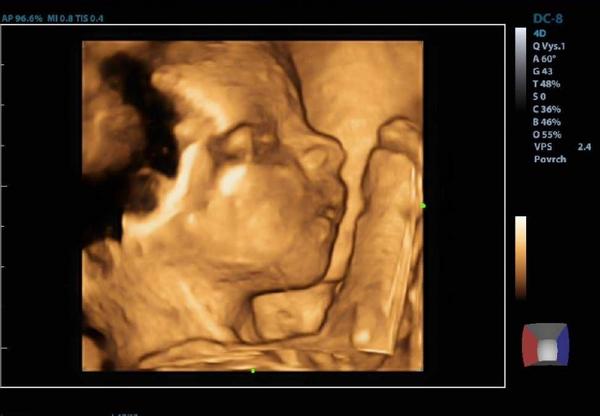

@tercasv ony ty cizí fotky na internetu jsou něco jiného, než když pak člověk vidí toho svého cvrčka 🙂 Mě tedy zase tak moc neoslovily přímo ty fotky - byť se nám povedly docela hezky, ale líbil se mi ten zážitek. Je vidět, jak se tam miminko tváří, jak zívá, dělá ksichtíky........🙂

Za mě fajn cesta do hlubin ...maminčina bříška - moc me bavilo, když jsem pak našla fotku ze 3D a fotku reálnou, které byly témeř totožné - tvář, výraz......

@tercasv ano určitě to za to stojí. Já byla několikrát, ještě lepší je 4D video nahrávka. Miminka ostatních se ti líbit nemusí, je to normální. Nechovás k nim žádný citový vztah. Tohle je vaše miminko, které milujete a určitě je to do budoucna krásná vzpomínka.

Musím říct, že to bylo super. Přesto, že nejsem zrovna hubená a mám placentu na přední straně, tak bylo mimčo krásně vidět. Oproti těm skoro mazaninám od gynekologa nesrovnatelné....

@tercasv Ja od toho moc neocekavala, premluvil me manzel, ze to zkusime, ze bychom treba litovali. Malej se nechtel ukazat oblicejem, takze jsme si dobre prohledli jeho zadek a naprosto presne vedeli, ze to bude kluk🙈 Pak se ale ukazal a stalo to za to. Mam fotku, kterou mam stale vytavenou na stole a rada se koukam, jak si byl po narozeni podobny, vcetne jeho mimiky😀 U me to tedy predcilo ocekavani, nejen ten vysledek, ale i ten zazitek byl fajn😀.